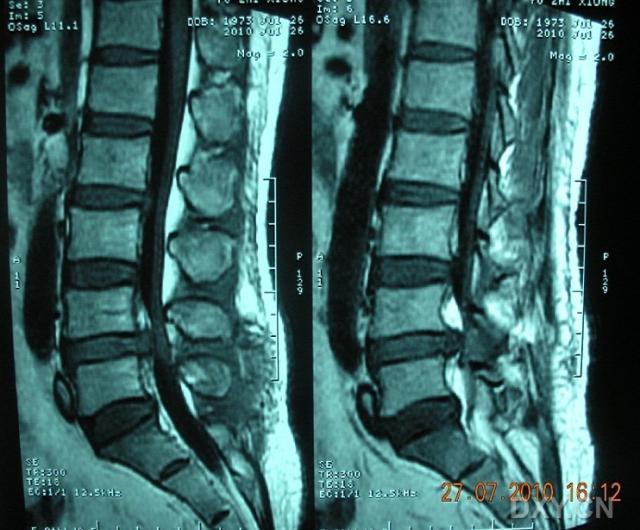

如有下列情况,是需要做固定的:

1、腰椎间盘突出合并腰椎滑脱、腰椎不稳的;2、腰椎间盘突出合并椎管狭窄(多数有间歇性跛行的症状),需行大范围减压的;3、术后腰间盘突出复发二次手术的;4、高位的腰椎间盘突出;5、二个以上多节段的腰间盘突出,手术需要广泛减压;

6、极外侧型间盘突出,手术需要破坏小关节的;

7、年龄大于45岁,需要承担较强体力劳动的;

我们采用4cm小切口显微镜下单纯腰椎间盘突出症经开窗摘除髓核手术,患者第二天即可下床行走,不仅解决了腰腿痛问题,同时费用明显降低。